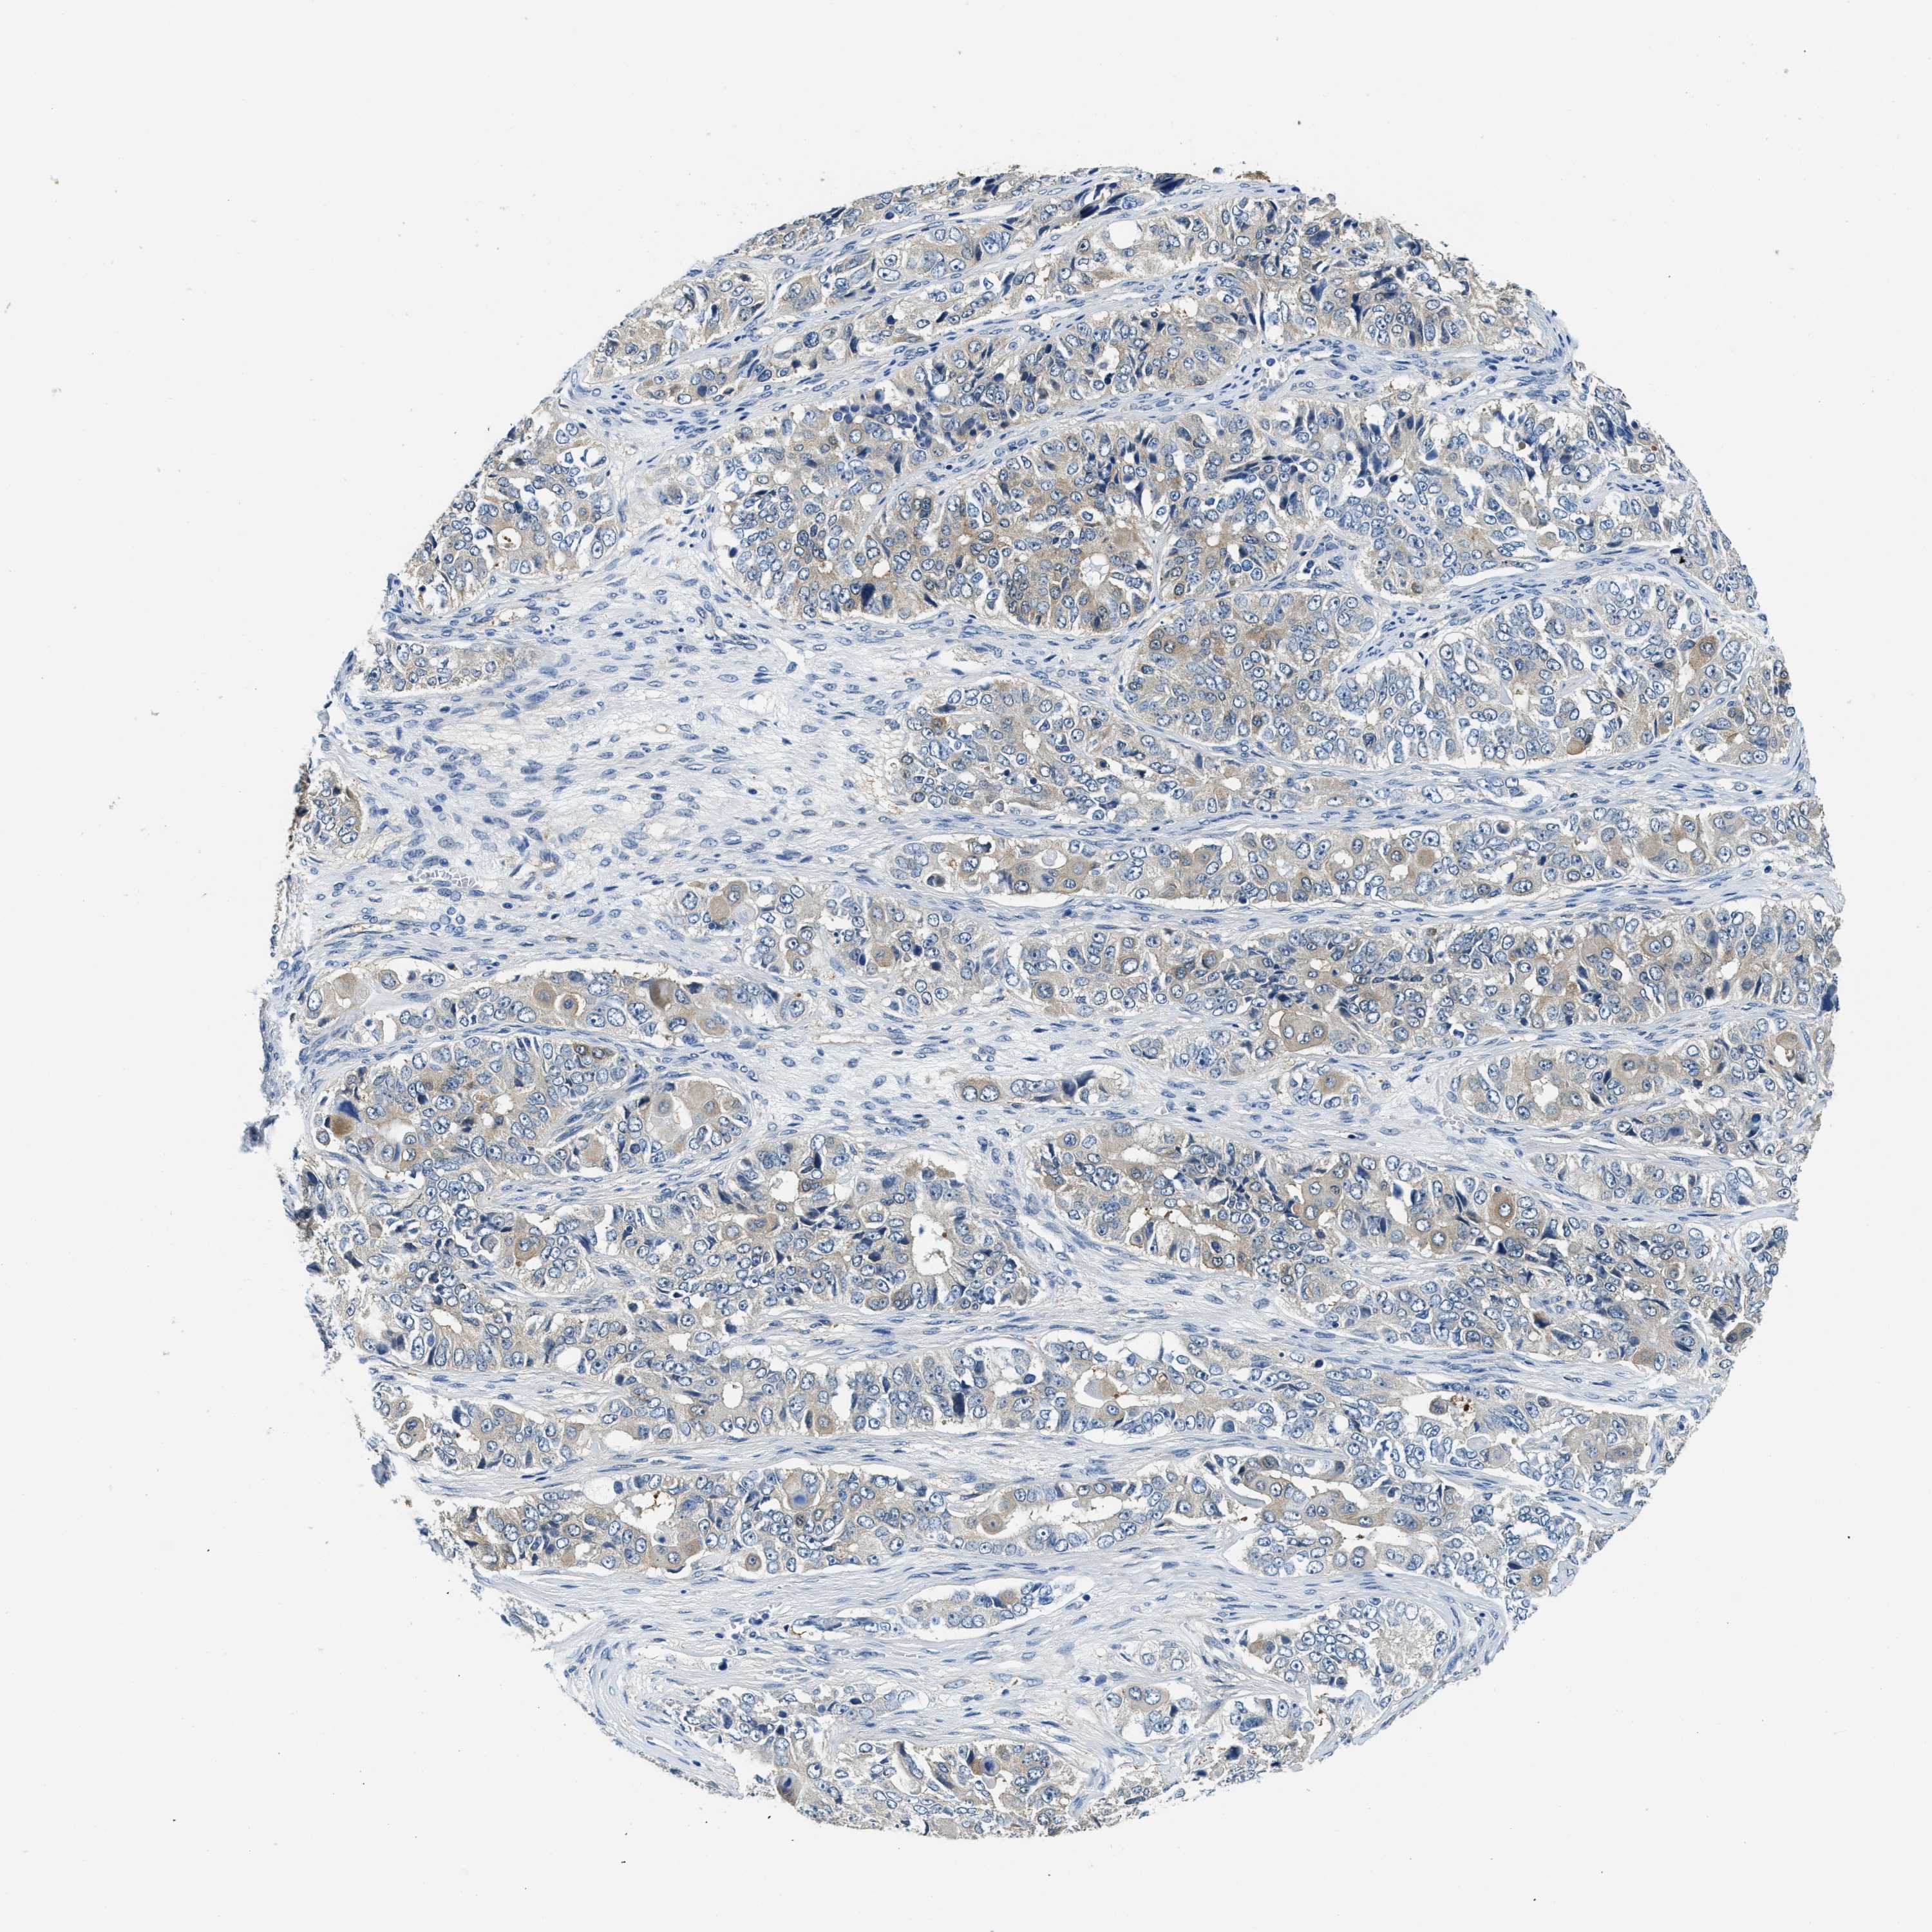

OVARIAN CANCER - Protein expressioni

A mouse-over function shows sample information and annotation data. Click on an image to view it in a full screen mode. Samples can be filtered based on level of antibody staining by selecting one or several of the following categories: high, medium, low and not detected. The assay and annotation is described here.

Note that samples used for immunohistochemistry by the Human Protein Atlas do not correspond to samples in the TCGA dataset.

Antibody stainingi

Antibody staining in the annotated cell types in the current human tissue is reported as not detected, low, medium, or high, based on conventional immunohistochemistry profiling in selected tissues. This score is based on the combination of the staining intensity and fraction of stained cells.

Each image is clickable and will lead to virtual microscopy that enables deeper exploration of all samples and also displays staining intensity scores, fraction scores and subcellular localization as well as patient and tissue information for each sample.

Antibody HPA018116

Staining

High

Medium

Low

Not detected

Intensity

Strong

Moderate

Weak

Negative

Quantity

>75%

75%-25%

<25%

None

Location

Nuclear

Cytoplasmic/membranous

Cytoplasmic/membranous,nuclear

Cystadenocarcinoma, serous, NOS

Carcinoma, endometroid

Cystadenocarcinoma, mucinous, NOS

Carcinoma, NOS